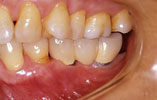

CASE1

歯を一本だけ失った場合 審美的・機能的に回復

インプラント埋入前

インプラント埋入後

インプラントに

セラミッククラウンを装着

1本のインプラントによってあたかも自分の天然歯のように自然に感じられます。

骨の「萎縮」も心配なく本来の骨量を維持できます。ブリッジを入れる時のように健康な隣の歯を削る必要がありません。